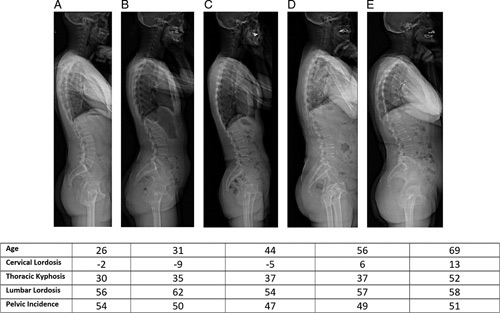

- Slight cervical kyphosis in young people is NORMAL

Cervical lordosis from C2 to C7: −0.4±12.7°

Thoracic kyphosis (TK) from T4 to T12: 37.4±10.9°

L1–S1 lumbar lordosis (LL): −57.4±11.3°

Pelvic incidence (PI): 52.0±10.7°

- Thoracic kyphosis increases with age

- Cervical lordosis increases with age to compensate for increasing thoracic kyphosis. Therefore, Cervical SVA (C2-C7 SVA) is maintained with age